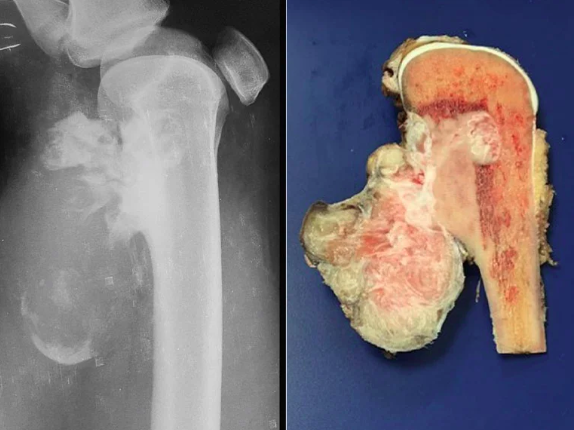

O osteossarcoma é um tipo de câncer que se desenvolve a partir do tecido ósseo e pode atingir qualquer osso do corpo. É mais comum em crianças e adolescentes, especialmente na fase do chamado “estirão” do crescimento.

Geralmente, o tumor aparece nos ossos longos, como o fêmur, a tíbia, especialmente perto do joelho, e o úmero, próximo ao cotovelo. Cerca de 80% dos casos estão ligados ao fêmur.

O tratamento combina quimioterapia e cirurgia para remoção do tumor. A quimioterapia pode ser feita antes ou depois da operação, dependendo do caso.